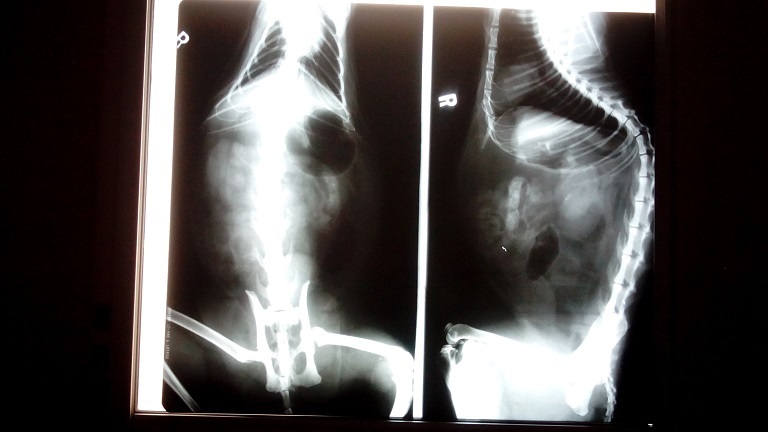

主題: 被車擦撞腳脫臼的喵 申請者姓名: 林玉真 花色: 申請日期: 2014-08-25 20:28:45 申請者部落格: 申請者臉書網址: 所在縣市/合作醫院: 新北市/成蹊動物醫院 治療費用: 5800元 需求人數: 7人 已結案 (2014-08-26 15:03:36) 報名人員: Manto Tin. x7(已付款)、 候補人員: 動物病情說明: 此貓是我長期餵養的浪貓(助紮編號04958)也是協會助罐浪貓之一,8月15日餵貓時貓咪趴在車下不動也不進食覺得有異狀立刻先補捉回家初步勘查,臉跟左後大腿有外傷應該是被車擦撞造成,送醫照X光左後腳有脫臼現象 由於貓貓已有3天不願進食所以醫院先上點滴及進行灌食 腸道內也發現有異物還好4天後有自行排出 腳脫臼的部位慢慢形成骨膜包覆(因開刀日後也不保證不會再脫臼)住院五天後食慾已有恢復 腳需要長期休養出院後由我帶回自行照顧也不會再放回原地 也感謝協會安排醫院就醫 醫療費用也請大家幫忙~感恩